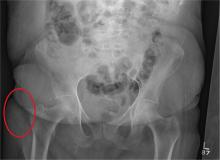

After a fall, an 80-year-old woman is brought to the emergency department for evaluation of hip pain. She was getting out of bed when she slipped, fell, and landed on her right hip; bearing weight now is painful. She denies hitting her head. The patient’s vital signs are normal. Her medical history is significant for hypertension and diabetes. Inspection of the hip reveals no obvious deformity or shortening. The right lateral aspect of the hip exhibits mild swelling and decreased range of motion secondary to the pain. You order a pelvic radiograph, which is shown. What is your impression?

The radiograph shows no acute fracture or subluxation. Diffuse osteopenia is present. Increased density is noted within the soft tissue lateral to the trochanteric portion of the right femur; this likely represents a contusion or hematoma.